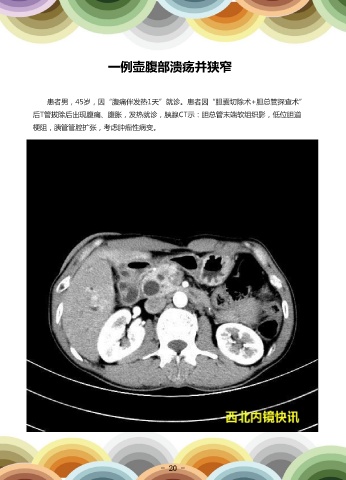

一例壶腹部溃疡并狭窄

患者男,45岁,因“腹痛伴发热1天”就诊。患者因“胆囊切除术+胆总管探查术”                                         超声内镜检查:壶腹部溃疡并狭窄;乳头稍增大(FNA穿刺活检)。超声内镜FN

后T管拔除后出现腹痛、腹胀,发热就诊,胰腺CT示:胆总管末端软组织影,低位胆道                                         A穿刺病理提示:“十二指肠乳头”黏膜慢性活动性炎伴乳头状腺瘤形成及局灶上皮中

梗阻,胰管管腔扩张,考虑肿瘤性病变。                                                              度不典型增生。患者出院随访中。